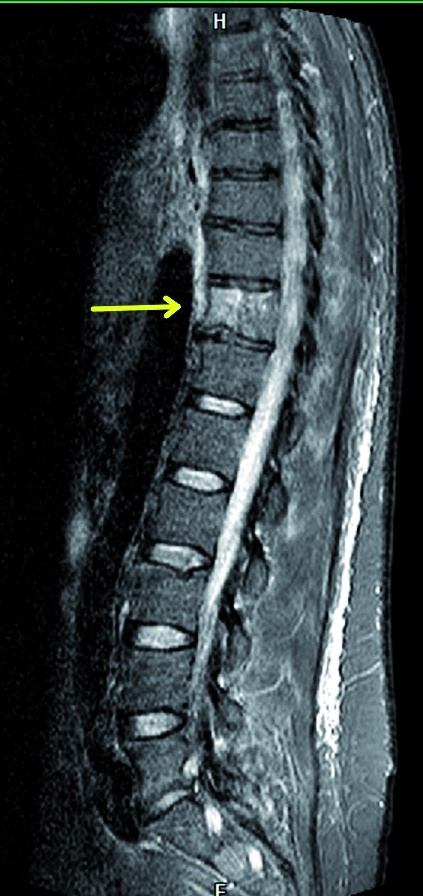

Die Röntgenaufnahme des Thorax zeigte pneumonische Infiltrate beidseits ohne Nachweis von Kavernen (Abbildung 2). CT[4] Thorax und Abdomen mit Kontrastmittel erbrachten den Nachweis fein- und grobfleckiger pneumonischer Infiltrate und Pleuraergüsse beidseits sowie eine Hepatosplenomegalie. Im MRT[5] BWS/LWS (nativ und mit Kontrastmittel) stellte sich das Bild einer isolierten Spondylitis des BWK 11 mit zirkulärer paravertebraler Entzündungsreaktion ohne spinale und Diskusbeteiligung dar (Abbildung 3). Der Ausschluss von Herzklappenvegetationen erfolgte durch eine transösophageale Echokardiographie. Bronchoskopisch wurde zäh-putrides Sekret für die mikrobielle Untersuchung gewonnen; infektiologisch konnten Malaria, Tuberkulose, Brucellose, Leptospirose, Hepatitis, eine HIV- und Legionelleninfektion ausgeschlossen werden. Die Sonographie des Abdomens war bis auf eine Hepatosplenomegalie unauffällig. Laborchemisch fielen bei Aufnahme erhöhte Entzündungswerte, eine Linksverschiebung im Differential-blutbild sowie

Zur Objektivierung der klinischen Befundbesserung wurden im Verlauf erneute Bildgebungen (Computer- und Magnetresonanztomographie) durchgeführt. Diese erbrachten korrespondierend zum klinischen Befund eine Rückbildung der Veränderungen im 11. Brustwirbel. Nach vierwöchigem stationären Aufenthalt konnte der Patient in die ambulante Weiterbehandlung entlassen werden. Der initial beobachtete Sklerenikterus und die Cholestase, deren Genese nicht abschließend geklärt wurde, waren bei Entlassung nicht mehr klinisch präsent.